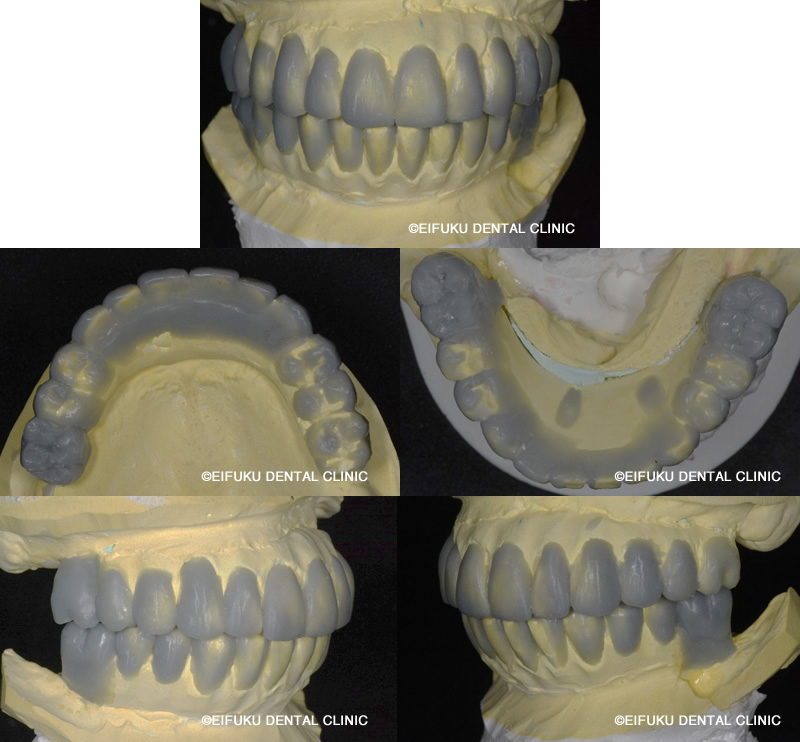

オールオン6(骨の状態によってはオールオン4)という技術を用いることによって、歯が1本もない患者さんでも手術をしたその日に歯が入り食事をすることが可能になります。

初診時の写真にあるように、咬む場所がなく、今まで流動食や舌で潰せる食べ物しか噛めない状況でした。

初診時には、咬合高径といって本来患者さんが歯がすべてあった状態での咬み合わせの高さが失われている方が多いです。そして、長い年月歯の無い状態で食事を続けていると脳が高さを失った状態をインプットしてしまいます。